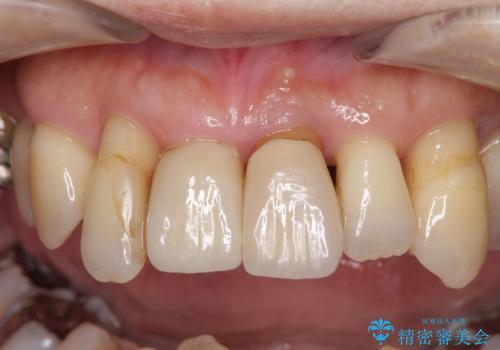

診察を行ったところ、重度歯周病の状態の上に上下の歯列が著しい叢生という状態でした。

歯周初期治療として抜歯や歯槽骨再生治療を行い、さらに歯周ポケット除去を行った後に矯正治療で歯列を整えて行くこととしました。

上顎口蓋からの堅い歯肉を移植する角化歯肉移植術を行いたかったのですが、体調不良から実施しなかったため、最終補綴物であるオールセラミッククラウンを装着した後に、知覚過敏や境目が見てしまうといった問題が一部で発生いたしました。